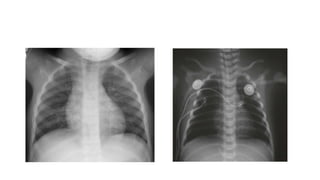

C. Imaging: The CXR may show

- cardiomegaly or a normal-sized heart,

- normal or diminished pulmonary vascularity.

- Disease specific findings.

D. The ECG most commonly shows RV predominance.

B. Cardiac signs: -prominent right ventricular impulse, a single, accentuated S2, and a murmur of TR. - In extreme cases, there may be hepatomegaly and signs of heart failure. C. Imaging: The CXR may show - cardiomegaly or a normal-sized heart, - normal or diminished pulmonary vascularity. - Disease specific findings. D. The ECG most commonly shows RV predominance.